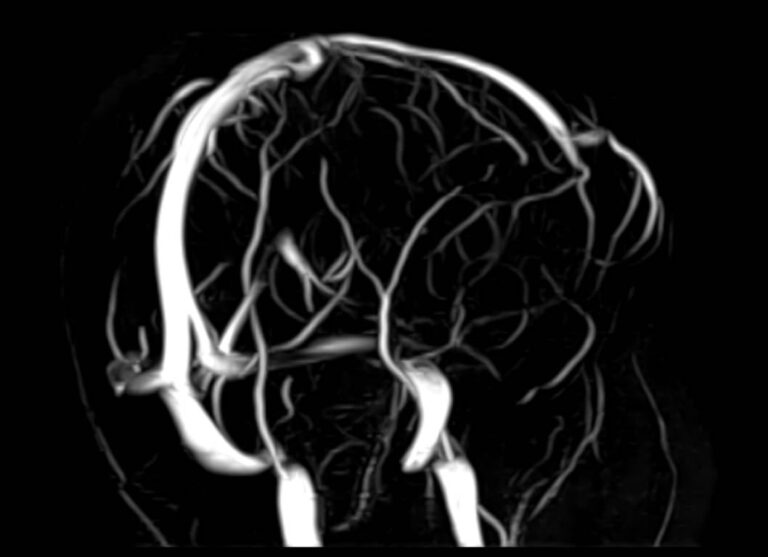

Магнитно-резонансная венография головного мозга позволяет детально изучить особенности анатомического и функциональной состояния венозного русла головы и шеи. С помощью данного исследования можно исключить многие серьезные заболевания сосудов головного мозга и начать своевременное лечение.